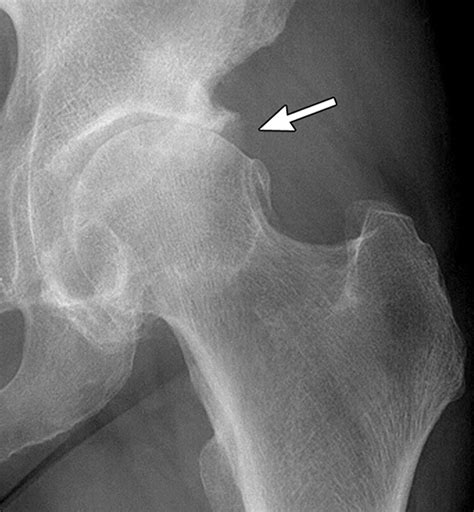

Lateral view of hip bone | Anatomy.app